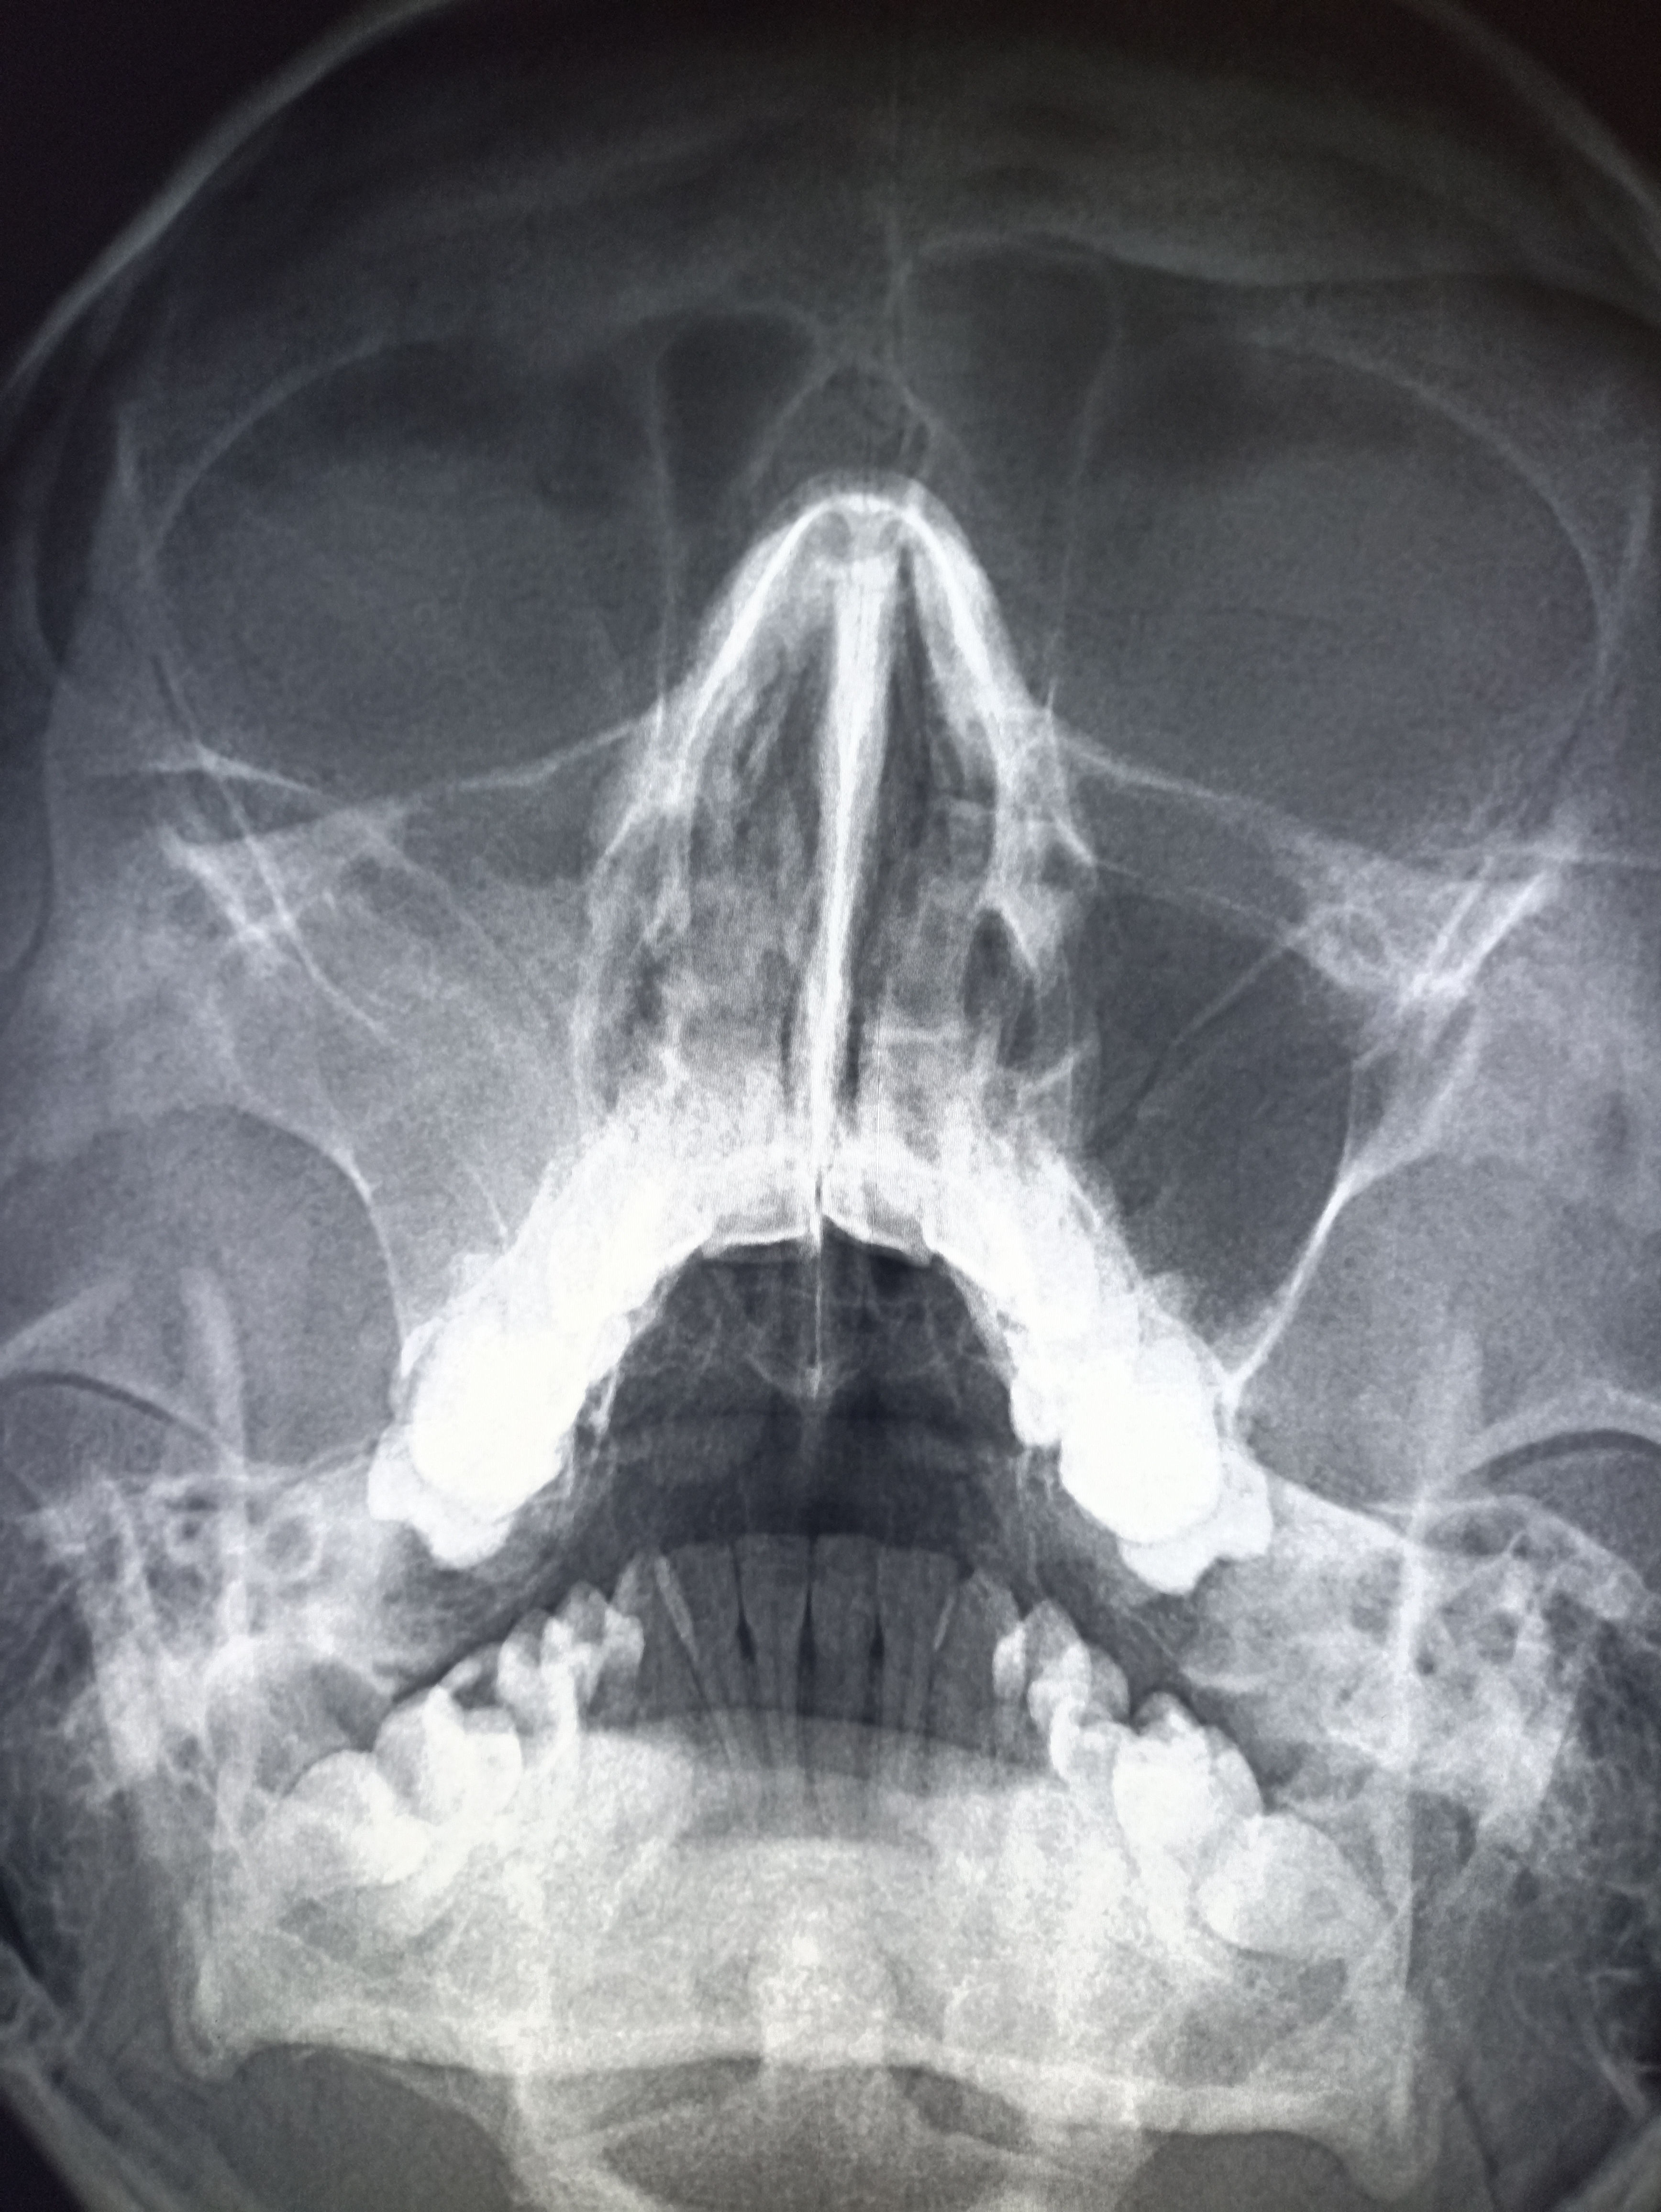

Аноним 16/10/25 Чтв 09:08:24 #19 №325599891

IMG20251016110751.jpg

Где пиздецомы?

>>325599891

тут явно что то справа. Там скобы после операции, туда отклоняется трахея (?) и средостение. Может часть легкого удалили?